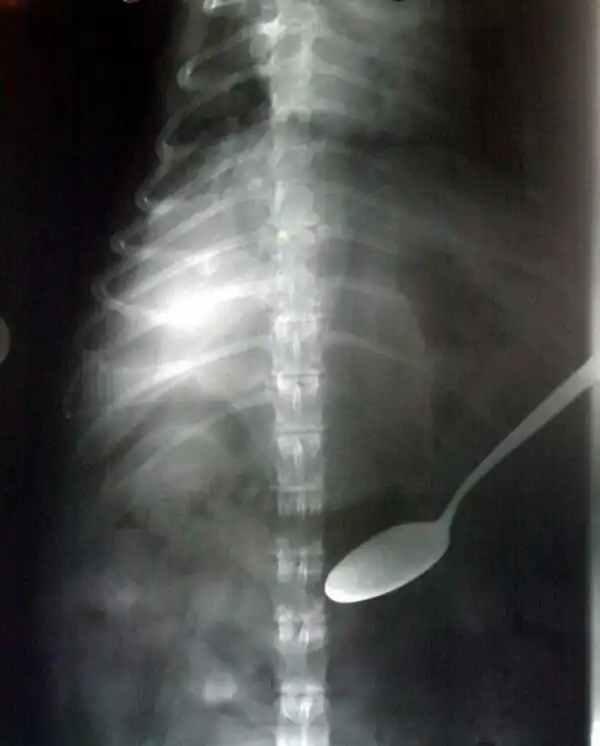

Спаниель полакомился ложкой. Без серьезных последствий